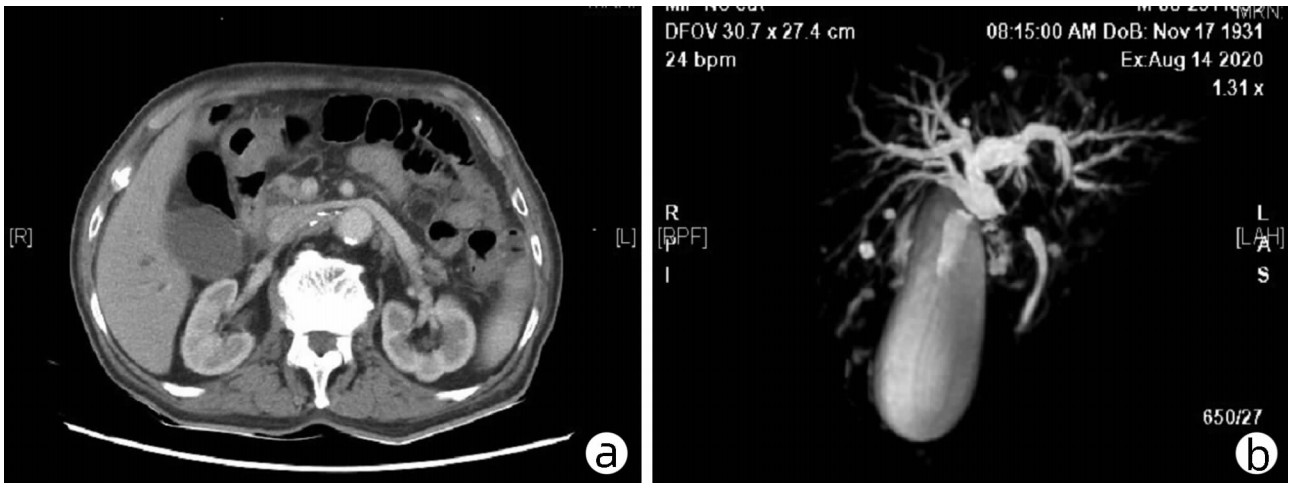

Conversion therapy for massive hepatocellular carcinoma: A case report

Sirou LI, Yuanlong ZHOU, Keliang LIU, Zhibo LIANG, Jinghua LI

2022, 38(7): 1612-1615. DOI: 10.3969/j.issn.1001-5256.2022.07.028

Abstract(963) HTML (407) PDF (2763KB)(77)

Abstract: